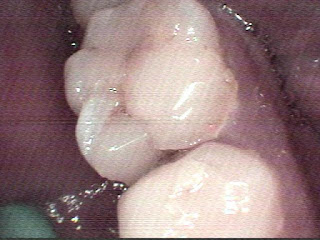

tooth no. 46

the caries weakened the cement filling